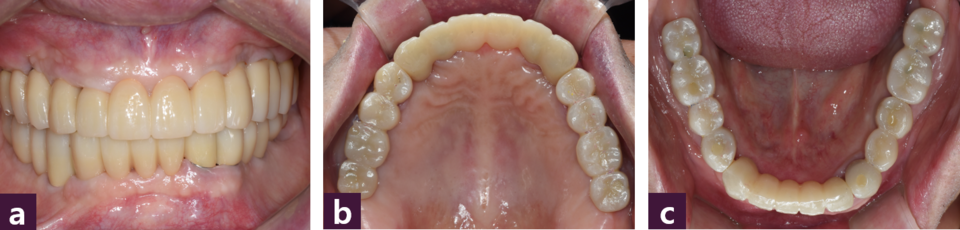

3개월 간의 고정성 임시보철물 사용기간 동안 경과 관찰과 교합 조정을 시행해 적 절한 심미성의임시 보철물이 안정적으로 기능하도록 하여 환자가 만족하였다. 또한, 임시 보철물 사용기간 동안 악관절의 이상 증상도 없었고 시멘트 유지형 임시 보철물의 탈락은 발생하지 않았으며 연조직 치유도 양호하였다.

식립 3개월 후 최종 보철물을 제작하기 위해 임시 보철물을 부분적으로 제거한 후 abutment level로 인상을 채득하고 교차 마운팅을 위한 바이트를 채득하여 상악 전치, 하악 전치, 하악 구치, 상악 구치 순으로 zirconia 보철물을 제작하였다 [그림 10].

본 환자는 각각의 임플란트축의 차이가 존재해 맞춤 지대주를 사용하였으므로 passive fit을 얻는데 주안점을 두어 시멘트 유지형 보철물로 수복하였다.

최종 보철물은 보철물의 passive fit, 청소성, 탈착 가능성의 측면을 고려하여 상악은 전치부와 구치부로 3분획하고 하악은 전치부, 우측 구치부, 좌측 소구치부, 좌측 대구치로 4분획하여 제작하였다.

완성된 상하 보철물을 구강내에 fit-checker를 이용하여 가착한 후 악간 관계를 채 득하고 pick up type 인상 채득 한 다음 반조절성 교합기에 리마운팅하여 교합조정을 시행해 전방 및 측방운동시 군기능 교합양식을 부여하였다 [그림 11].

완성된 최종 보철물을 구강내에 위치시키고 추가적인 교합조정 후 레진 강화형 글라스 아이오노머 시멘트(RelyX Luting cement, 3M, USA)로 최종 접착하였다[사진 12~15].